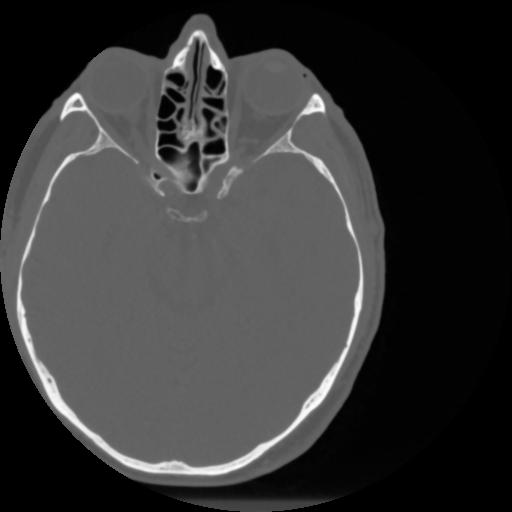

4 CEREBRO,,Vol,0.5,CEREBRO,,